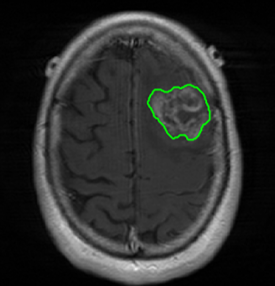

We argue that the sub-optimal paradigm of processing different abstractions within a single CNN pipeline can be remedied through the effective processing of information in a structured manner. Consequently, we devise strategies for disentangling the edge and texture information within a single training pipeline. Figure 2 illustrates how our proposed module, dubbed EG-CNN, can be paired with any existing CNN encoder-decoder to improve segmentation quality near intensity edges. We have applied our EG-CNN to the tasks of brain and liver tumor segmentation in medical images (Figure 3).

(1) Brain MR (2) Liver MR (3) Liver CT (4) Lung CT